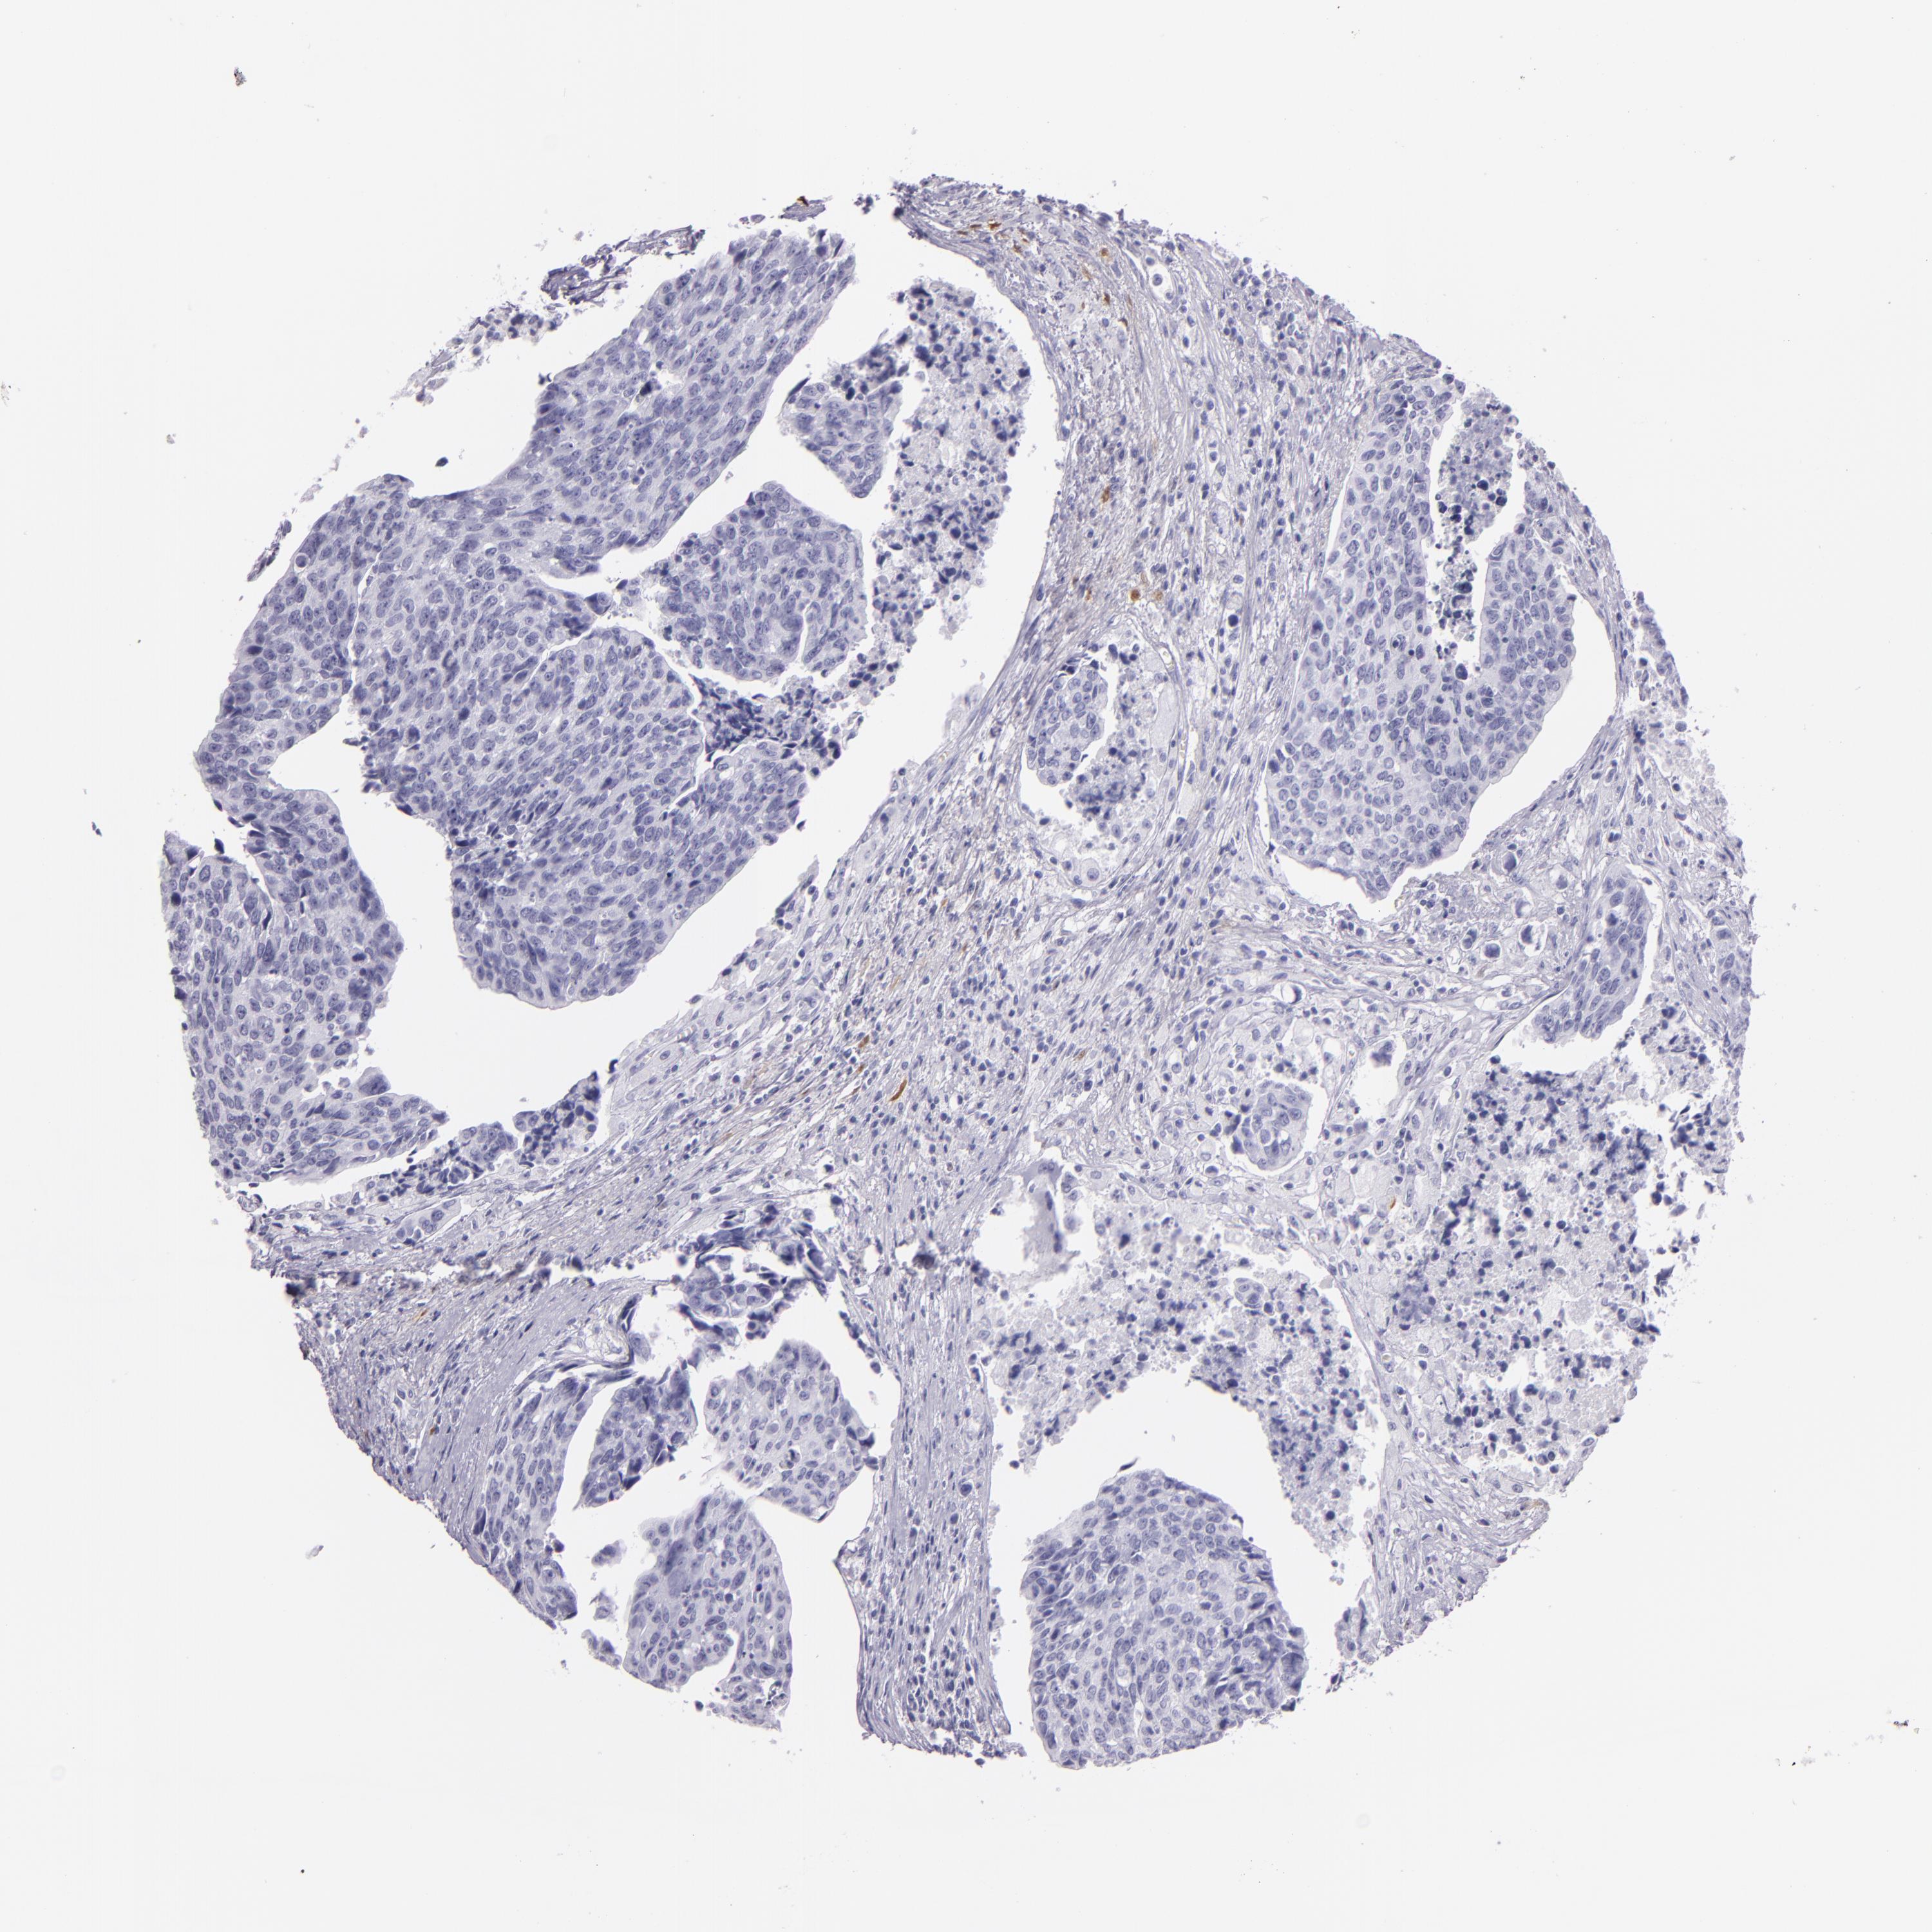

UROTHELIAL CANCER - Protein expressioni

A mouse-over function shows sample information and annotation data. Click on an image to view it in a full screen mode. Samples can be filtered based on level of antibody staining by selecting one or several of the following categories: high, medium, low and not detected. The assay and annotation is described here.

Antibody stainingi

Antibody staining in the annotated cell types in the current human tissue is reported as not detected, low, medium, or high, based on conventional immunohistochemistry profiling in selected tissues. This score is based on the combination of the staining intensity and fraction of stained cells.

Each image is clickable and will lead to virtual microscopy that enables deeper exploration of all samples and also displays staining intensity scores, fraction scores and subcellular localization as well as patient and tissue information for each sample.

Antibody CAB002161

Antibody CAB013056

Urothelial carcinoma, High grade

Urothelial carcinoma, Low grade

Adenocarcinoma, NOS